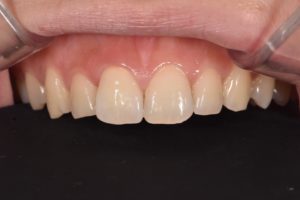

術後

詳細:前肢の審美障害を主訴に来院された患者さんです。上の前歯に過去に治療し不適合となったクラウンが入っており、その横の歯に欠けた跡がみられました。不適合のクラウンのみをやりかえると左右中切歯の幅がかなり差が生じてしまうことから、欠けている部分をダイレクトボンディングにて形態修正を行い、不適合クラウンはジルコニアセラミックで再治療することで審美障害を改善しました。

抜髄されてあった歯は打撲による外傷で歯が折れた過去があり、舌側に欠けて大きく歯が欠損していました。そこで、テンポラリークラウンにて歯肉のマネジメントを行い、シリコン印象材により丁寧に印象採得することで適合の良いクラウンを作ることができました。

また、模型上で事前にシミュレーションをすることで、ダイレクトボンディングにより欠けた部分の形態の再現が精度良くでき、審美的にも満足の行く治療となりました。